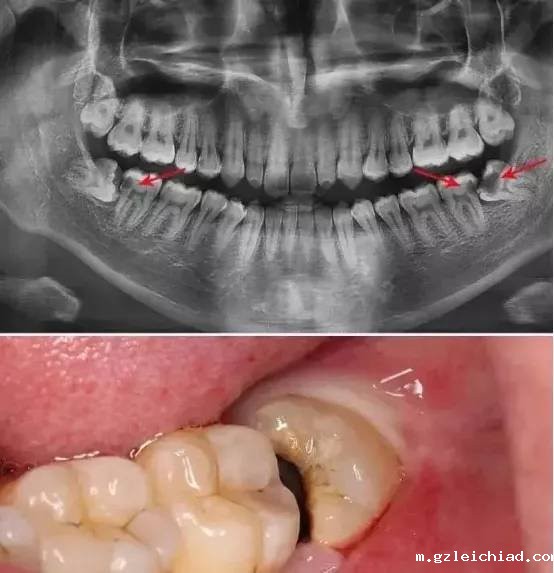

二是造成相邻牙的损害,常见于与智齿相邻的第二磨牙。

当智齿萌出不全如低位阻生时,相邻的第二磨牙远中颈部可因阻生智齿等局部因素导致龋坏,进而发展为第二磨牙牙髓炎及根尖周炎。                                                                                                                                                                                                                                         其中最凶险的莫过于智齿冠周炎,虽然它大都可以控制得当炎症逐渐消退,如果没有控制的好,会导致很严重的后果。每年我们科都会收治一些智齿冠周炎并发颌面间隙感染的病人住院,最严重的需要颌下切开排脓并转入ICU协助诊疗的。

智齿造成邻牙损伤也很普遍。因为它与邻牙容易形成间隙而存留食物残渣,较难清理,久而久之就会导致龋坏,轻则充填修复,重则导致牙髓炎需要根管治疗,最严重的甚至需要拔除。                                                                                                                                                                                                    那么,长了智齿一定要拔除吗?